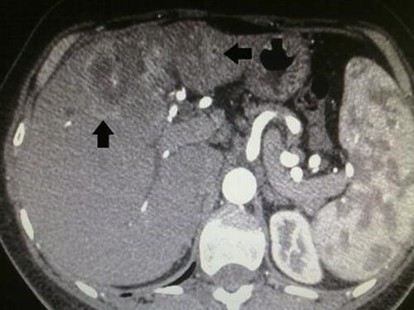

La evidencia de las lesiones hepáticas obedece tanto al número y localización dentro del hígado, como a la presencia o no de enfermedad extrahepática. Esto último es importante en el proceso de selección de aquellos pacientes a los que se les debe o no ordenar una cirugía hepática. En la tomografía sin contraste las metástasis suelen ser iso o hipodensas respecto del resto de parénquima, salvo en casos de sangrado o calcificación intralesional en que pueden ser hiperdensas. Podemos observar calcificaciones en metástasis de tumores mucinosos del tracto gastrointestinal o en metástasis de ovario, mama, pulmón, riñón y tiroides.(18) Las metástasis suelen tener el mismo comportamiento que el tumor de origen, suelen ser hipovasculares en tumores de colon, pulmón, adenocarcinoma de páncreas y en tumores de vejiga y próstata. Se observan lesiones hipervasculares en tumores primarios de tiroides, tumores neuroendócrinos (carcinoide, tumor de islotes pancreáticos, feocromocitoma) y en melanoma, cáncer renal, coriocarcinoma y sarcomas.(18-19)

Dentro de los patrones de reforzamiento de las metástasis lo más frecuente que podemos encontrar en fase arterial es la captación periférica y continua (por efecto de parasitación de la lesión y reacción desmoplástica/inflamatoria del parénquima adyacente), metástasis homogéneamente hipercaptantes (suelen ser menores de 1,5 cm), metástasis heterogéneas por fibrosis y necrosis central (> 3 cm) o con mínima captación periférica (lesiones hipovasculares).(18) En las fases portal y venosa tardía el patrón más frecuente es la captación progresiva incompleta. En menor grado se observan lesiones que se hacen isodensas con el resto de parénquima o persistencia de una mínima captación periférica (Anexo 17). El fenómeno de lavado (washout) periférico se ha descrito como hallazgo típico de metástasis, consiste en la desaparición del contraste en la periferia de la lesión en fases retardadas, es más frecuente en las metástasis hipervasculares, especialmente en tumores neuroendocrinos. Supone una mejor vascularización arterial y venosa en la periferia, donde se sitúa el tumor viable, respecto al centro de fibrosis o necrosis.(18-22)